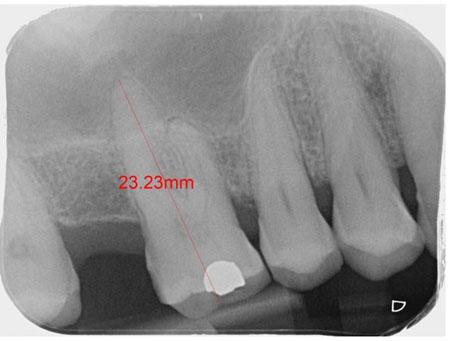

Case Report: The patient presented an increase in tissue volume in the papilla region between teeth 33 and 34, with no report of pain and with aesthetic impairment. Radiographically, no pathological changes were noted in bone and dental structures.